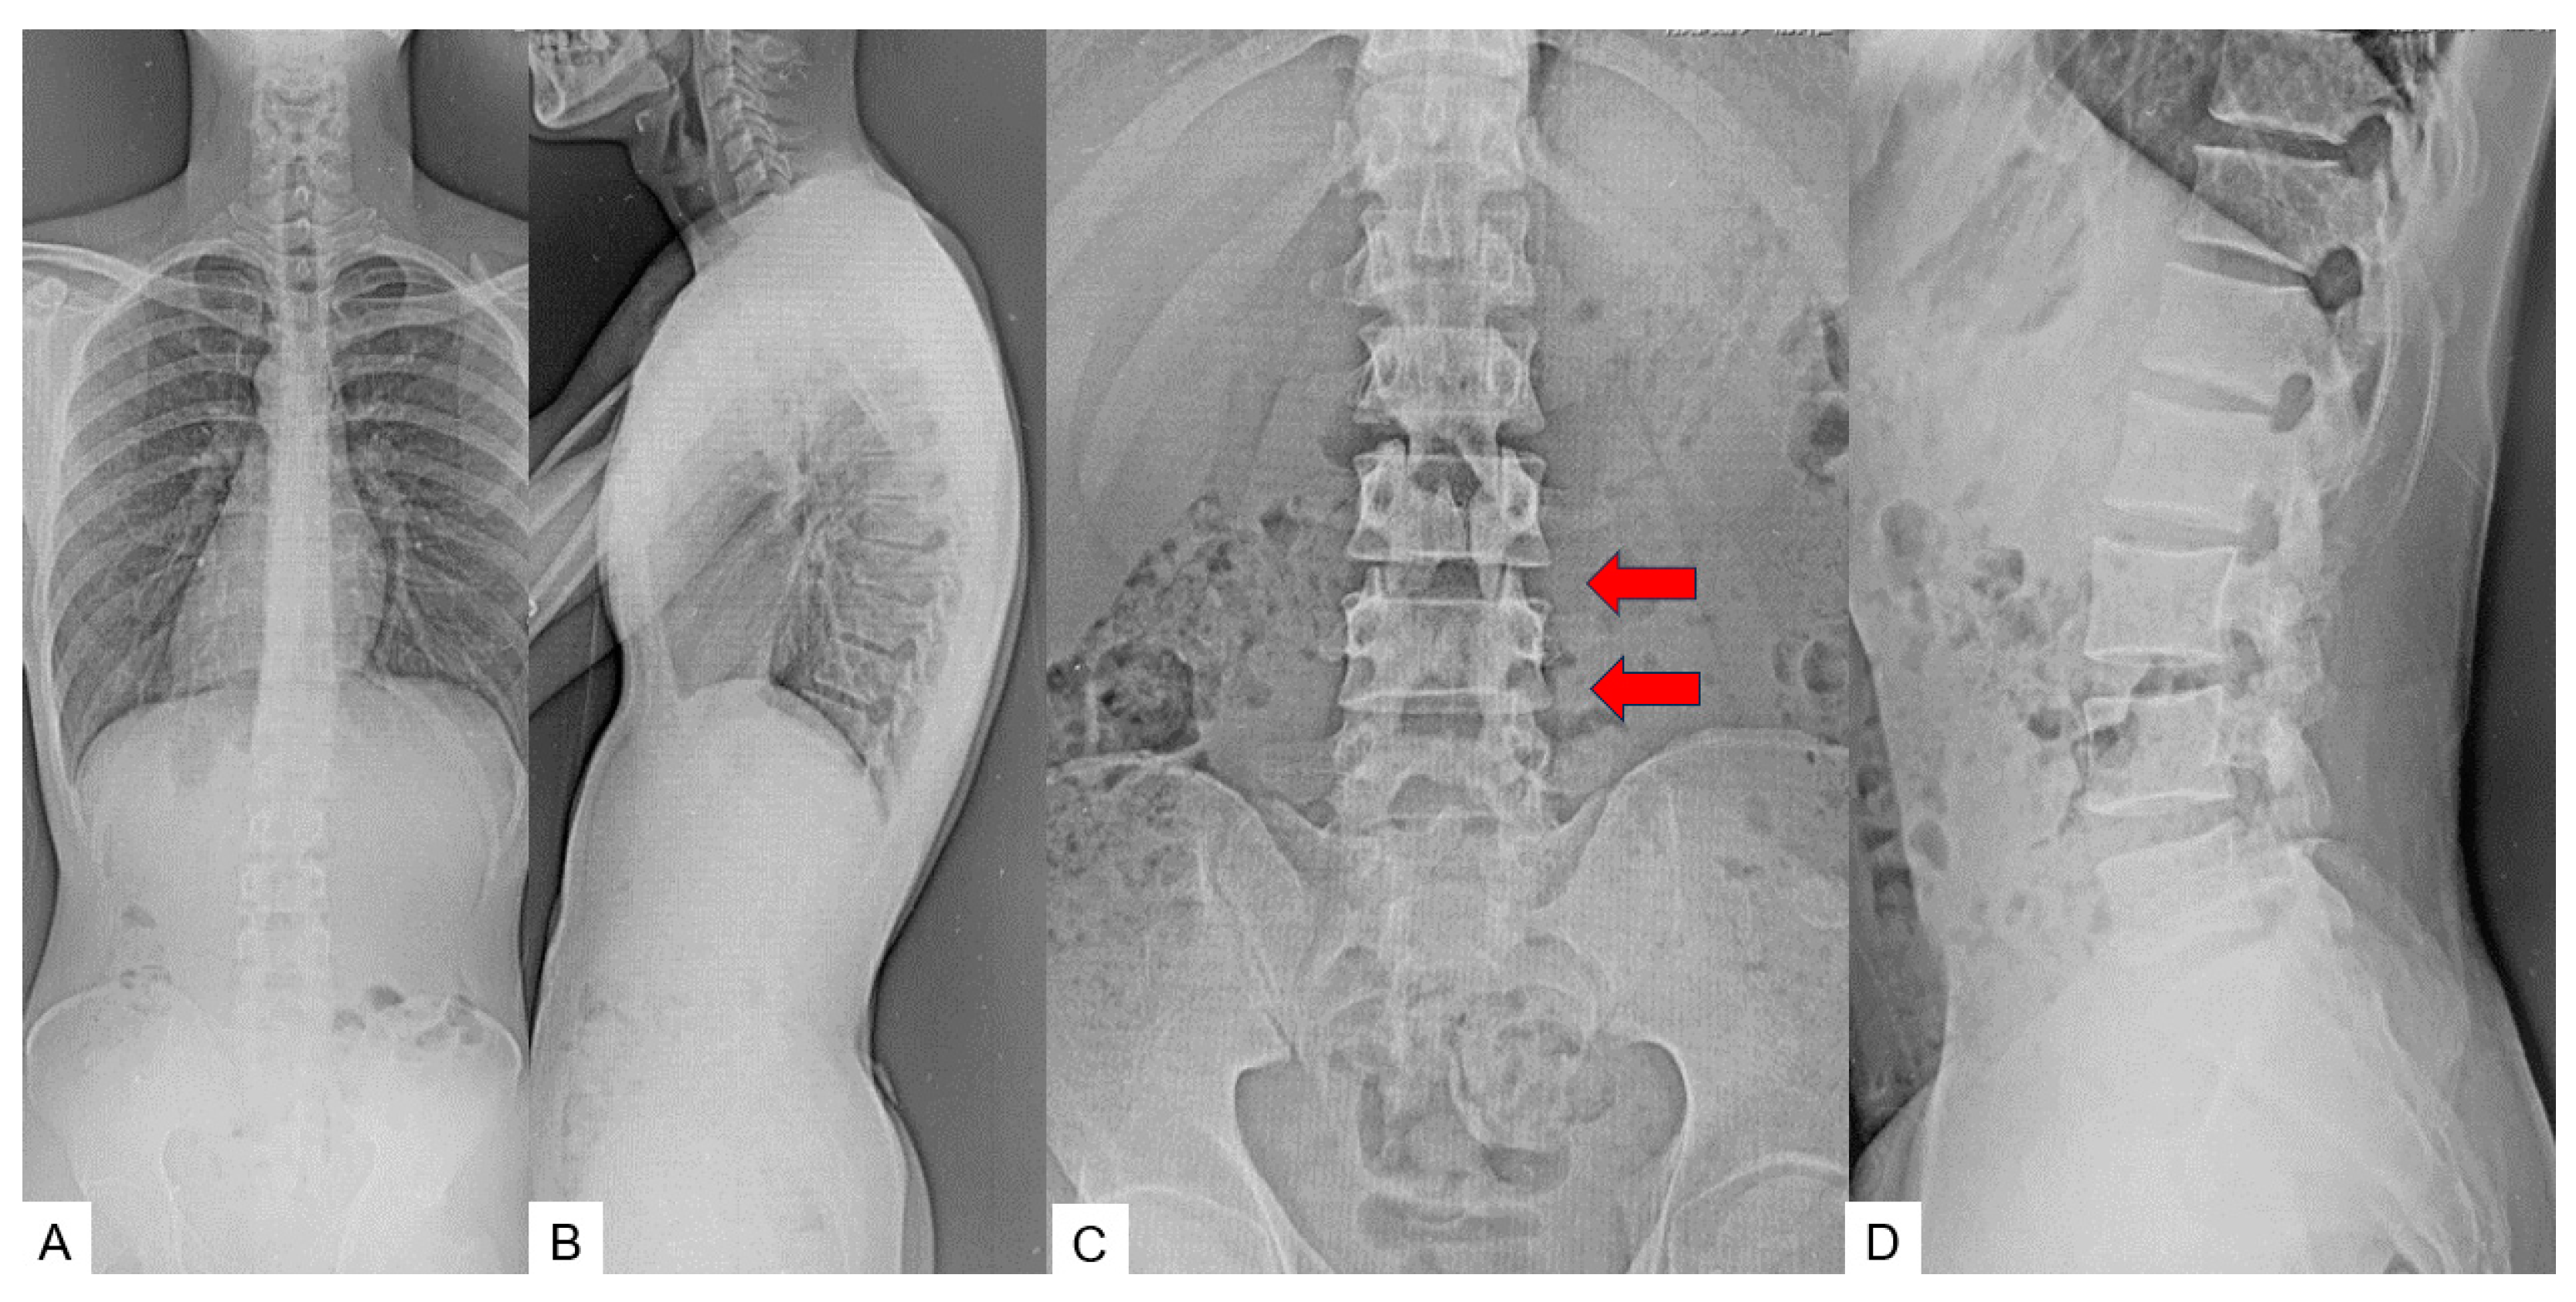

3. Case 2: 33-Year-Old Male, Tethered Cord Syndrome, Conventional Technique